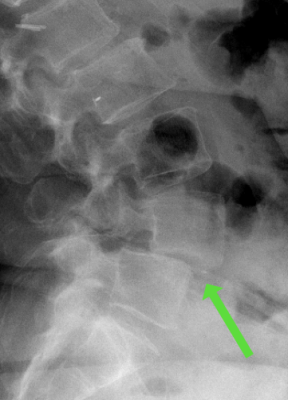

Spondylolisthese - Wirbelgleiten

Von einem Wirbelgleiten spricht man bei Verschiebung bzw. Verkippung zweier benachbarter Wirbelkörper gegeneinander. Eine Retrolisthese bezeichnet das Verschieben des kopfnäheren Wirbelkörpers gegenüber dem darunterliegenden Wirbelkörper nach hinten, analog wird das Gleiten des Wirbelkörpers nach vorn als Anterolisthese bezeichnet. Zu unterscheiden ist zwischen einem frühkindlich erworbenen Wirbelgleiten mit vorliegender Defektsituation im Zwischenwirbelbereich des Wirbelbogens (sog. Spondylolyse) und einem verschleißbedingten, degenerativen Wirbelgleiten mit intakten knöchernen Strukturen und begleitender Arthrose der kleinen Wirbelgelenke sowie Insuffizienz der Bandstrukturen.